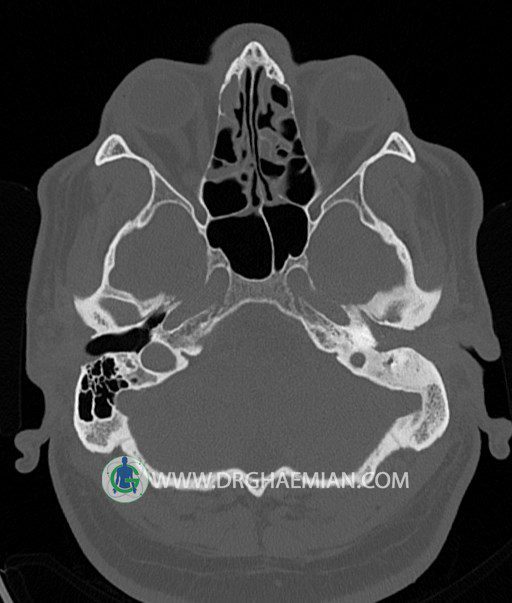

سی تی اسکن گوش داخلی به رادیولوژیست اجازه می دهد تا سطوح مختلف، یا اسلایس هایی از استخوان های که از جمجه به گوش می روند را از طریق امواج ایکس چرخشی مشاهده کند. در این کیس اودیت مدیا، ماستوئیدیت مزمن، اوتیت خارجی، انحراف سپتوم بینی، کونکا بولوزا و افزایش ضخامت سینوس ها مشاهده می شود.

در HRCT از استخوان تمپورال با مقاطع آگزيال ، ساژيتال و کرونال ظريف ( 0.6 mm ) :

– نماي کوکلهآي دو طرف با 2.5 دور گردش مجرا

– نماي cochlear aqueduct

– نماي semicircular canal خلفي ، لترال ، فوقاني و وستيبول

– استخوانچه هاي گوش داخلي شامل malleus ، incus و stapes (دنسيتي و رديف استخوانچه ها )

– نماي oval window و round window ، tympanic cavity ، attic و کانال گوش داخلي

– کانال عصب فاشيال و مسير ان از ناحيه کانال گوش داخلي ، geniculate ganglion تا محل خروج ان از stylomastoid foramen

– نماي tympanic membrane ، کانال ICA ، بولب جوگولار دو طرف

در حد طبيعي است .

– اپاسيتي گوش مياني چپ ناشي از وجود دانسيته نسج نرمي دراطراف استخوانچه ها همراه با اروژن اسکوتوم و

استخوانچه ها بدون جابجايي در رديف استخوانچه ها مشهود است که مطرح کننده اوتيت مديا همراه با نشانه

هاي مشکوک به کولستئاتوم مي باشد .

– اپاسيتي و اسکلروزيس ماستوئيد چپ نشانه ماستوئيديت مزمن

– اپاسيتي کانال گوش خارجي ناشي از دانسيتي نسج نرمي مطرح کننده external otitis

– انحراف سپتوم مياني بيني به راست

– کونکا بولوزا در کونکاي مياني چپ و

– افزايش ضخامت مخاطي در سينوس هاي اتموئيد و ماگزيلاري

اپاسيته